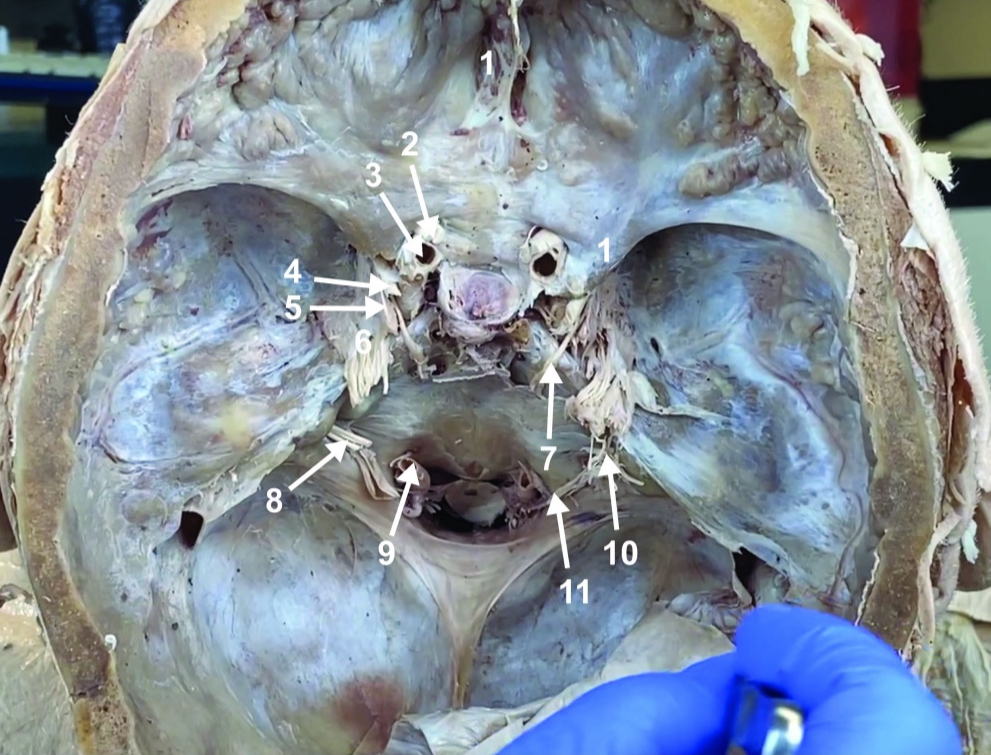

Foramen magnum

Foramen ovale

Foramen spinosum

Cribiform plate

Optic n. (CN II)

Internal carotid a. (ICA)

Occulomotor n. (CN III)

Trochlear n. (CN IV)

Trigeminal n. (CN V)

Abducent n. (CN VI)

Facial and vestibulocochlear n. (CN VII and VIII)

Vertebral a.

Glossopharyngeal and vagus n. (CN IX and X)

Root of spinal accessory n. (root of CN XI)

Ophthalmic division of CN V (CN V1)

Maxillary division of CN V (CN V2)

Mandibular division of CN V (CN V3)

Foramen rotundum

Foramen ovale

Trochlear n. (CN IV)

Abducent n. (CN VI)